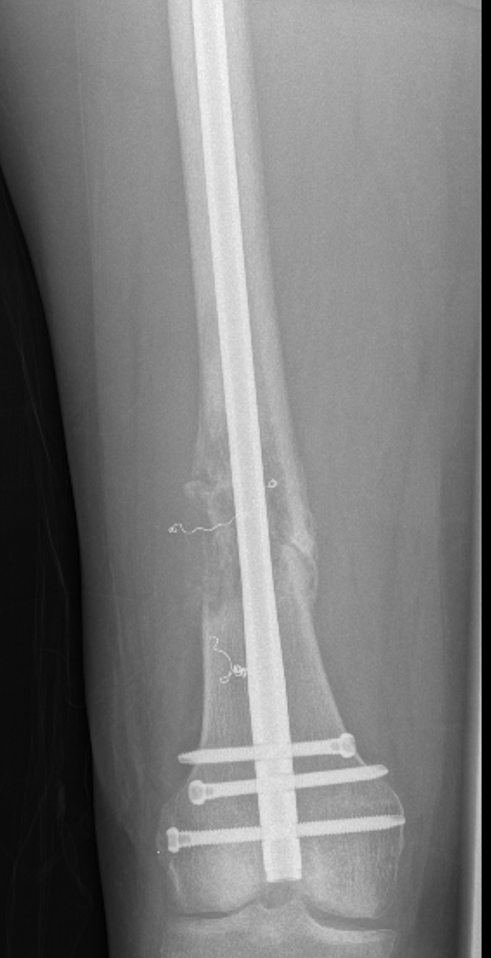

Subtrochanteric / Femoral shaft metastasis

Management

Reconstruction nail

- consider cement

- consider venting

Durability

- 217 patients treated with cephalomedullary nails for proximal femoral metastasis

- revision surgery required in 10%

- more common with survival > 7 months

Cement

- 43 patients with IMN + cement of femur and humerus versus 27 IMN

- lower pain scores with cement

- some reduction of metastasis progression with cement